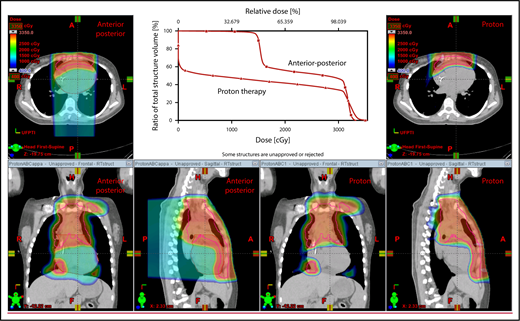

The plan target is the CTV; when the treatment area is affected by breathing motion, the plan target is the internal target volume (ITV), which encompasses the motion of the CTV depicted on 4D CT scans. Alternately, if treatment is to be given with DIBH, an ITV can be derived from the positions of the CTV reproduced from multiple DIBH scans. For lateral beam shaping, margin expansion to form the PTV accounts for setup uncertainty, and interfractional variability in anatomy is applied to the CTV/ITV. Patient-specific beam collimators conform the dose laterally to the PTV, with a margin for penumbra. Depending on the target depth and adjacent tissue, these margins vary from 5 to 10 mm. Range compensators are designed for each beam to conform the dose distally to the CTV/ITV. Range compensator smearing within a radius appropriate for setup tolerances and tissue motion is applied to account for proton range changes caused by density changes in the beam path. In addition, along each beam, distal and proximal margins are set to the CTV/ITV to compensate for proton range uncertainties, as described under “Range uncertainties due to density variations.” Multiple beams (compared with 1 beam) can be used to increase dose conformality and reduce dose uncertainties by spreading the beams in various directions. The preference is to use anterior or posterior fields, rather than both, because of the need to avoid unnecessary beam through the heart (Figure 4).

An example of an approach using 2 anterior fields with proton therapy, which can better spare the heart and esophagus (right) compared with an anterior/posterior approach (left).

With regard to field arrangements, the PBSPT technique for an anterior upper mediastinal and lower neck target usually requires 1 (repainted) or 2 anterior fields. For more complex target volumes, targets can be divided into 2 or more parts (eg, neck CTV, mediastinal CTV, and axillary CTV), and a multifield plan can be used (Figure 5). For cases that involve lower (posterior) and upper (anterior) mediastinal targets, a combination of posterior and anterior fields can maximally spare the heart and lungs (Figure 6). For upper neck targets, lateral or posterior fields can avoid the oral cavity/salivary structures. For axillary targets, a posterior field can help to spare breast tissue. Although these various field arrangements can be used in PSPT, gradient matching is simpler in PBSPT when the fields overlap or oppose, obviating the need for feathering.

Plans for PBSPT with a single-field uniform dose and a gradient match, with anterior and posterior beams used to treat disease that involves the bilateral upper neck and the mediastinum (disease anterior to the right heart).